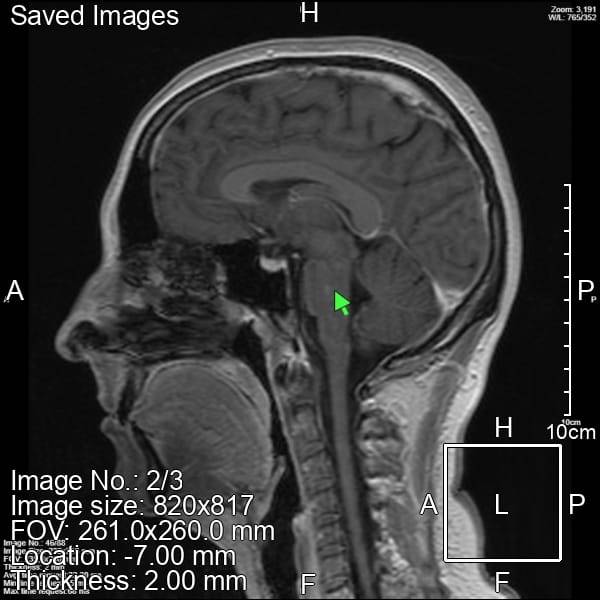

МРТ головы это конечно ужасный аттракцион, но там всё хорошо.

По КТ есть лимфоузел справа (метостаз, новый рак, или просто воспаление❓❓❓) поинтересовалась с своего врача в онко, сквозь зубы ответили только наблюдать, посмотрим, что завтра скажут.